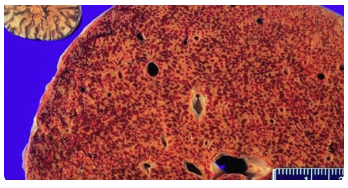

What does this liver show?

a. Bowel metastases

b. Liver Failure

c. Macronodular cirrhosis

d. Micronodular cirrhosis

e. Nutmeg liver

A

Macronodular cirrhosis